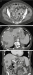

Schima W, Aiginger C Aktuelle Bilder: Gedeckt perforierte Sigmadivertikulitis mit multiplen pylephlebitischen Leberabszessen Journal für Gastroenterologische und Hepatologische Erkrankungen 2015; 13 (2): 18-19 Volltext (PDF) Übersicht

Filmsequenz zu Abbildung 7: Film 3 Kontrastmittelsonographie der Leber im Dualbildmodus (rechts: CEUS; links: normale B-Bild-Sonographie): Die Abszesse zeigen keinen Kontrastmittel- Wash-in oder -Wash-out im Zentrum. |